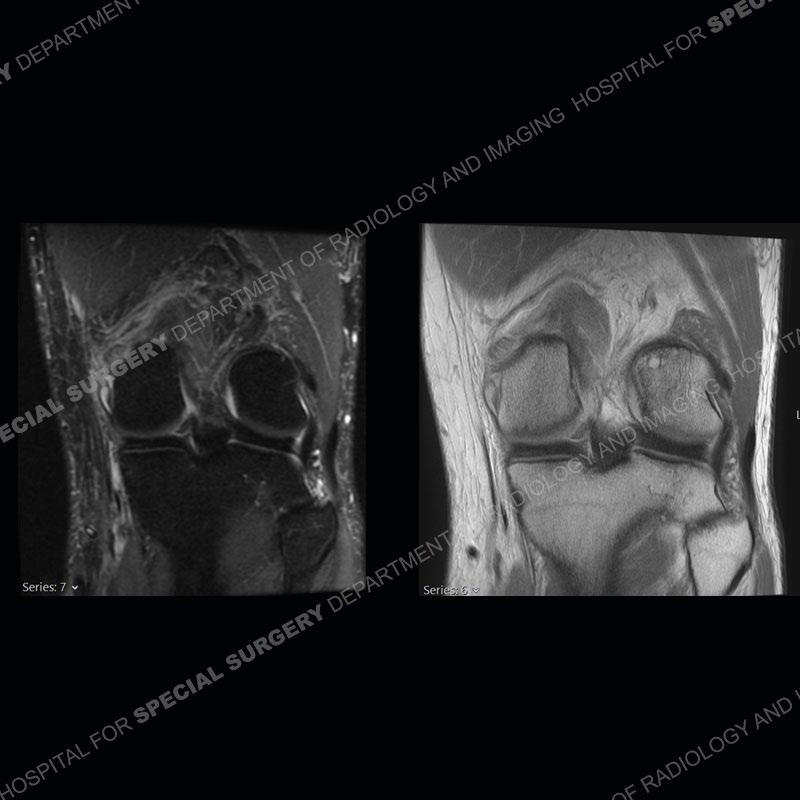

Findings

The radiographs show degenerative change of the medial compartment and a varus knee, but they are not germane to this case. No acute bony injury is present. The MRI shows edema of the posterior medial knee/soft tissue and a focal area of a partially disrupted low signal structure. The details are kept at a minimum in the findings of this case on purpose.

Diagnosis: Partial Disruption Medial Head Gastrocnemius (MHG)

The findings were kept purposefully vague as identifying the structures early on takes away a lot of the diagnosis. An uncommon entity and one of which we do not see a lot. Enthesopathic changes and tendinosis are seen as are distal MHG injuries, but proximal tears are rarely present. This case highlights a number of points. One, it almost always comes down to anatomy. Perhaps not a structure we normally spend too much time on, except save for diagnosing a Baker’s cyst, but knowing where this structure and all structures exist in all three planes is imperative. Second, when you think you are making a “call” or finding that you have never made before, step back and think is this just the abnormal presentation of a common pathology. That situation arises much more frequently. Third, if you look at it once, twice, and probably a third time and are confident in your odd or very rare diagnosis, stick to your guns. Especially, when it comes down to anatomic structures, the proof will be in the images.

Fourth, use all imaging planes and different pulse sequences to make your diagnosis. The edema highlighted in this case can be seen as the obscuration of fat on the PD images but is much easier to perceive as the high signal on the IR pulse sequences. The actual disruption of the MHG myotendinous junction is only able to be seen on the axial images. On the sagittal and coronal images, we get a sense something is wrong but hard to be exact. Lastly, when you look at a study and something just seems off (as I would say the sagittal and coronal images do with that dark band of tissue posteriorly), listen to yourself and go through the study slowly and meticulously. Most of the time you will find you were right, and something indeed is present.